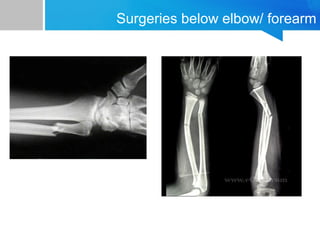

Surgeries below elbow/ forearm

Strategy for forearm/ both bones is……

AXILLARY

BLOCK